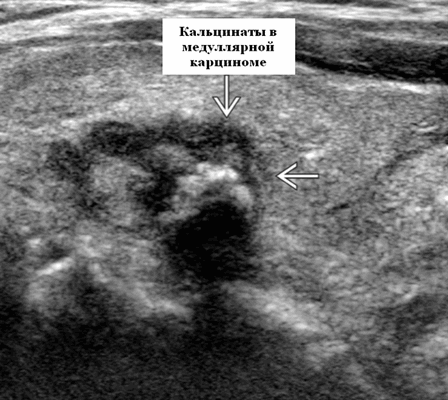

- Гипоэхогенная солидная опухоль, часто хорошо выраженная, но может иметь инфильтративные границы. Эхогенные очаги в 80-90%, представляющие отложение амилоида и связанную кальцификацию. Эхогенные очаги обычно плотные и грубые с затенением по сравнению с папиллярным раком

Оттенки серошкального УЗИ медуллярного рака, первичная опухоль. Одиночное или множественное или диффузное поражение обеих долей (особенно семейного типа). Расположена преимущественно в боковых верхних 2/3 железы в спорадической форме. Гипоэхогенная солидная опухоль, часто хорошо выраженная, но может иметь инфильтративные границы. Эхогенные очаги в 80-90%, представляющие отложение амилоида и связанную кальцификацию. Эхогенные очаги обычно плотные и грубые с затенением по сравнению с папиллярным раком.